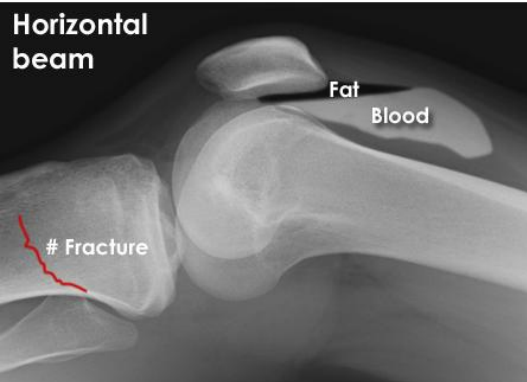

you examine this x-ray and identify a fracture as well as associated blood and fat in the joint cavity, what is this phenomenon called

Lipohaemoarthrosis

posterior fat pad is visible on a lateral xray of elbow, identify this phenomenon, why it occurs and what is likely to also be found on xray

Positive sail sign

Visible posterior fat pad occurs when joint effusion (from injury) fills olecranon fossa, psuhing the posterior fat pad out and making it visible

A fracture is likely to be found if there is +ve sail sign